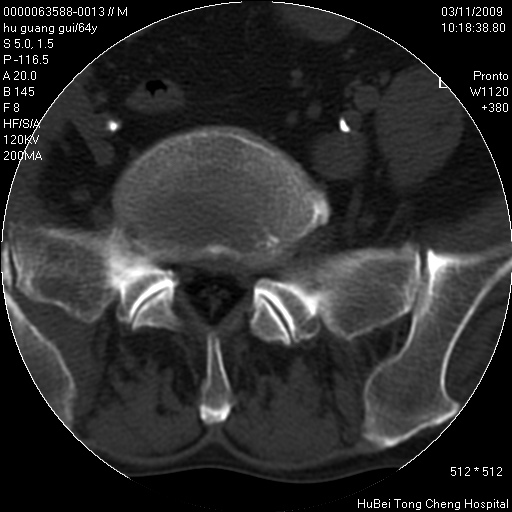

患者 男,64岁。腰痛十余天。(临床未提供其他病史)

临床诊断:腰痛原因待查(腰椎间盘突出症?)。

腰椎间盘ct轴位平扫(层厚5mm,层距4mm),图像如下:

右侧骶骨侧块骨侵蚀,骶髂关节骨性关节面破坏,并见软组织肿块,考虑骨转移瘤可能,进一步检查。

2.右侧骶骨侧块骨侵蚀,骶髂关节骨性关节面破坏,并见软组织肿块,考虑:脊索瘤,骨转移瘤可能,进一步检查。

1)腰椎退行性变,l4—5椎间盘膨出。2)骶骨右侧块骨转移瘤可能,3)水平骶椎。建议作一步检查。